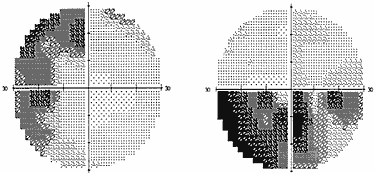

Рис. 1. Полная битемпоральная гемианопсия (автоматическая статическая периметрия) При наиболее часто встречающемся срединном варианте расположения хиазмы опухоль начинает сдавливать центральные перекрещенные волокна нижней поверхности хиазмы, идущие от носовых половин сетчатки. Клинически это проявляется появлением дефектов в верхних височных квадрантах поля зрения на обоих глазах – начальный хиазмальный синдром. Следует отметить, что дефекты в поле зрения поначалу можно выявить только с помощью цветных объектов, красного и зеленого. Исследование поля зрения на цвета более чувствительно, чем кинетическая периметрия на белый цвет. Острота зрения на этом этапе развития заболевания, как правило, сохраняется нормальной. Диски зрительных нервов обычной окраски. Постепенно, по мере роста опухоли, усугубляются битемпоральные дефекты поля зрения, начальный хиазмальный синдром переходит в развернутый хиазмальный синдром с полным или почти полным выпадением височных половин поля зрения. Появляется побледнение дисков зрительных нервов преимущественно в височной половине – развивается первичная нисходящая атрофия зрительных нервов. Важно знать, что изменения на глазном дне наступают спустя месяцы от момента развития первых дефектов поля зрения. Нередко, к сожалению, пациенты не фиксируют внимания на периферических дефектах в поле зрения и обращаются к офтальмологу только тогда, когда появляется понижение остроты зрения. Справедливости ради следует сказать, что порой и врачи не придают должного значения жалобам пациентов в случае сохранной остроты зрения и/или нормального диска зрительного нерва. Пациенты годами наблюдаются и лечатся у офтальмологов по поводу атрофии зрительного нерва. Понижение остроты зрения имеет место при воздействии опухоли на интракраниальный отрезок зрительных нервов, когда в процесс вовлекается папилло–макулярный пучок. Это происходит либо при непосредственном сдавлении зрительного нерва опухолью, либо в результате смещения его опухолью и придавливания нерва к серповидной связке или костным структурам интракраниального отверстия зрительного канала. Клинически симптом воздействия на интракраниальный отрезок зрительного нерва проявляется центральной или парацентральной скотомой. Но чаще это сочетается с периферическими височными дефектами поля зрения. Понижение остроты зрения возможно и в результате распространения височного дефекта поля зрения на центральную зону. Понижение остроты зрения может быть на одном или на обоих глазах. Сочетание понижения остроты зрения на одном глазу или на обоих, но разной степени выраженности, и битемпоральных дефектов поля зрения приводит к развитию асимметричного хиазмального синдрома, свидетельствующего об асимметричном росте опухоли. Понижение остроты зрения, которое появляется прежде или в относительно короткий срок после развития битемпоральных дефектов поля зрения, указывает на преимущественный рост опухоли кпереди – супраселлярно–антеселлярно или о заднем расположении хиазмы. При таком расположении хиазмы опухоль локализуется перед хиазмой, воздействуя в первую очередь или преимущественно на интракраниальные отрезки зрительных нервов. Внимание пациента также могут привлекать парацентральные битемпоральные скотомы. Острота зрения при этом бывает высокой. Наличие таких дефектов поля зрения свидетельствует о сдавлении задне–верхних отделов хиазмы, вблизи расположения папилло–макулярного пучка. Подобная симптоматика имеет место при росте опухоли интраселлярно и преимущественно кзади – супраселлярно–ретрохиазмально или при переднем расположении хиазмы. Характерной первой жалобой пациентов при таком варианте роста опухоли может быть жалоба на затруднение при чтении. Следует, однако, оговорить, что такой тип зрительных расстройств при аденоме гипофиза встречается достаточно редко. В силу различных причин, в частности, из–за строения диафрагмы турецкого седла, опухоль может распространяться не столько кверху, сколько латерально, в сторону кавернозного синуса – латероселлярный рост. Зрительные нарушения, которые присутствуют при этом росте опухоли, чаще представлены асимметричным хиазмальным синдромом со значительным, вплоть до практической слепоты, понижением остроты зрения на одном глазу. Может также развиться одноименная (односторонняя) гомонимная гемианопсия (рис. 2) в результате воздействия опухоли на зрительный тракт. Дефекты поля зрения появляются в половине поля зрения на стороне, противоположной локализации опухоли. Офтальмологи должны быть внимательны, поскольку дефекты поля зрения при латероселлярном росте опухоли и развитии асимметричного хиазмального синдрома или гомонимной трактусной гемианопсии появляются в носовой половине поля зрения на глазу на стороне преимущественного роста опухоли (рис. 3). Это может спровоцировать ошибочную диагностику глаукомы.

Рис. 3. Начальная левосторонняя гомонимная гемианопсия (автоматическая статическая периметрия) Помимо зрительных расстройств, характерным для латероселлярного направления роста опухоли является наличие глазодвигательных нарушений в результате либо сдавления медиальной стенки кавернозного синуса опухолью, либо непосредственной инфильтрацией опухолью структур кавернозного синуса. Несмотря на то, что глазодвигательные расстройства при аденоме гипофиза встречаются значительно реже, чем зрительные расстройства, от 1,4% до 4,5% по данным различных авторов, значимость их высока, в особенности если ими манифестирует опухоль. Чаще поражается глазодвигательный нерв. Начинается процесс с птоза или полуптоза верхнего века. Ограничение подвижности глазного яблока вверх, вниз развивается позднее. Зрачковая функция, нередко бывает сохранной или страдает незначительно. Полная офтальмоплегия – явление редкое и обычно развивается остро в случае кровоизлияния в опухоль. Небольшой (1–3 мм) экзофтальм – еще один симптом, который может свидетельствовать о латероселлярном росте опухоли. Он развивается в ответ на затруднение оттока крови по венам глазницы в кавернозный синус в случае инфильтрации его опухолью. Другой причиной экзофтальма является непосредственное распространение опухоли в глазницу, обычно по венозным коллекторам, через верхнюю глазную щель. Однако следует заметить, что это явление достаточно редкое. -Диагностика и лечение аденом гипофиза Диагностика аденомы гипофиза в настоящее время не представляет особых сложностей. Помимо рутинной краниографии, при которой, как правило, имеют место характерные признаки опухоли этой локализации (увеличение размеров турецкого седла, расширение его входа, выпрямление спинки), процесс диагностируется с помощью КТ и МРТ (особенно значимо при микроаденоме) головного мозга. Специфическая радиоиммунологическая техника обеспечивает определение концентрации гормонов в сыворотке крови, вырабатываемых передней долей гипофиза. Иммуноцитологическая техника в сочетании с данными светового и электронного микроскопа способна идентифицировать эти гормоны в ткани опухоли. Арсенал лечебных мероприятий при аденомах гипофиза достаточно большой. Возможные методы лечения аденомы гипофиза: - прямое хирургическое вмешательство (транссфеноидальный и транскраниальный доступы); - радиохирургию протонным пучком; - медикаментозное лечение парлоделом. Телегамматерапия в настоящий момент практически не применяется. Выбор типа лечения остается за нейрохирургами и эндокринологами. Прогноз восстановления зрительных функций после лечения аденом гипофиза, в том числе и хирургического, зависит от нескольких факторов. Помимо величины, распространенности и преимущественного роста опухоли, особенностей хирургического удаления опухоли, большое значение имеют характер, степень и длительность зрительных нарушений до начала лечения, выраженность атрофического процесса в зрительных нервах, т.е. стадии зрительных нарушений (ранняя или поздняя), что, в свою очередь, напрямую связано с топографо–анатомическим расположением опухоли. Все это свидетельствует о большой ответственности офтальмолога в своевременной диагностике аденомы гипофиза и реабилитации пациентов после лечения. -Практические рекомендации При жалобах пациента на зрительные нарушения первостепенное значение имеет тщательное исследование поля зрения для выявления характера дефектов поля зрения. При этом уместно вспомнить высказывание Бинга и Брюкнера: «результаты точного исследования поля зрения нередко выводят на путь правильной топической диагностики и в особенности ранней (!) диагностики», которое, несмотря на совершенство современных методик исследования зрительных функций, в полной мере сохраняет свою актуальность. При наличии атрофии зрительного нерва так называемой «неясной этиологии» в обязательном порядке следует провести КТ или МРТ головного мозга. При выявлении объемного образования в хиазмально–селлярной области в первую очередь показана консультация в нейрохирургическом учреждении. Лечение В данном случае была проведена операция костно-пластическая трепанация черепа в правой лобной области – удаление опухоли от 21.05.2003г, под общей анестезией. Последствием операции явилось неизбежная правосторонняя аносмия. В послеоперационном периоде отмечается значительное улучшение состояния. Прогноз В отношении жизни, в отношении работоспособности, выздоровления: благоприятный. Дневники